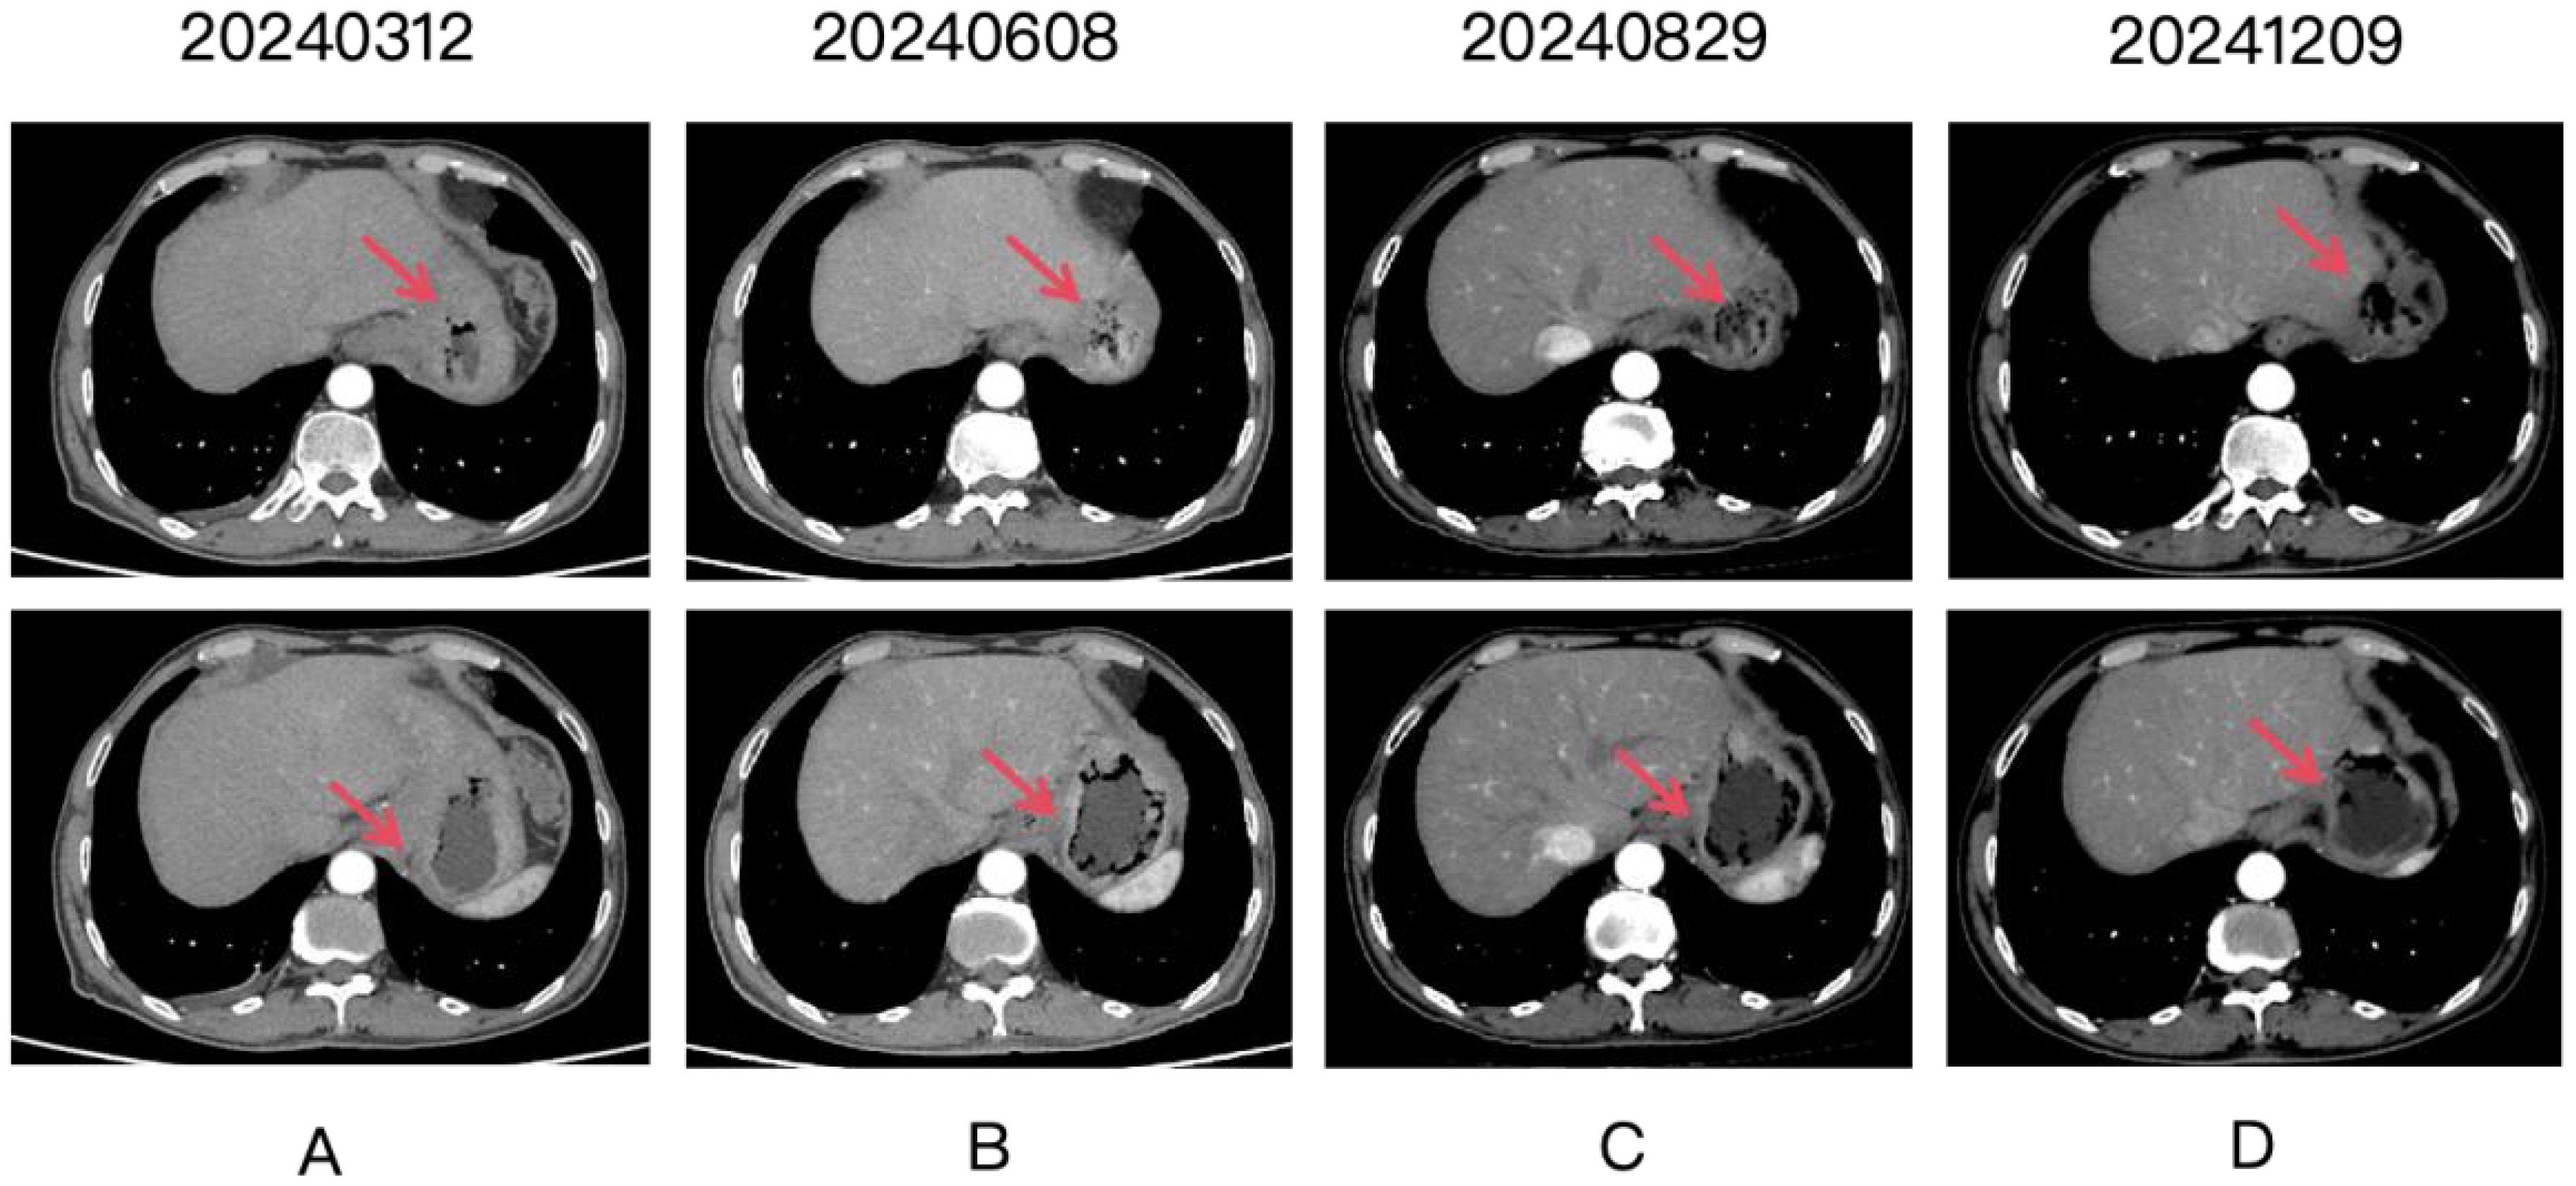

CT scan images show four panels labeled 20240312, 20240608, 20240829, and 20241209, arranged in two rows labeled A and B. Each panel shows a transverse view of the abdomen with red arrows pointing to a specific area in the liver, indicating changes in density or structure over time.

Figure 2. Four panels labeled (A-D) show CT scan images over time, with dates 20240312, 20240608, 20240829, and 20241209. Each panel contains two images. Red arrows point to the gastric lesion, which shows a partial response after treatment.

A patient undergoing routine medical examination in March 2024 presented with upper gastrointestinal bleeding on gastroscopy (March 11, 2024), revealing: Mucosal congestion, edema, and ulceration at the gastroesophageal junction and gastric fundus/corpus (suggestive of linitis plastica), pending pathological confirmation. Pathological diagnosis of poorly differentiated adenocarcinoma (biopsy from greater curvature of gastric body). Immunohistochemistry (IHC): CK (Broad Spectrum+), CEA (+), p53 (focal weak positivity), Ki-67 (>80% positivity), CDX-2 (focal weak positivity). MMR proteins: MSH2(+), MSH6(+), MLH1(+), PMS2(+). HER-2 (heterogeneous expression: partial 2+, partial 3+). Abdominal CT was obtained in Tianjin Union Medical Center of Nankai University (March 12, 2024): Gastric mass consistent with gastric carcinoma (cT3NxM1); Omental metastases with adherence to adjacent bowel loops; Hepatic metastases (Segments II, IV, VII; largest nodule: 0.7 cm); Enlarged right cardiophrenic angle lymph node (recommended follow-up); Minimal ascites; Benign cystic lesion in pancreatic tail (recommended follow-up); Hepatic cyst (Segment IV); Bilateral renal cysts. The patient was diagnosed with stage IV gastric adenocarcinoma with hepatic and omental metastases. First-line therapy commenced in March 2024 with: Inetetamab (300 mg IV, day 0), Tislelizumab (200 mg IV, day 0), Oxaliplatin (100 mg/m² IV, day 1), Capecitabine (1.5 g twice daily, days 1-14). Following 8 cycles of combination therapy, radiographic assessment confirmed a partial response (Figures 24). The patient subsequently received 3 cycles of maintenance therapy with inetetamab and tislelizumab. As of the last follow-up in March 2025, the patient remained progression-free with a progression-free survival (PFS) exceeding 12 months.